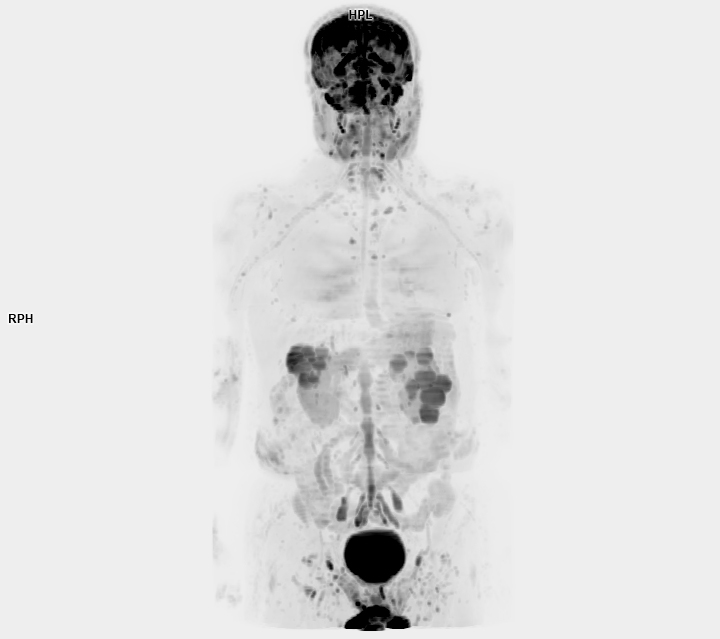

• 3 TESLA MR ÇEKİM GÖRÜNTÜLERİ

3 Tesla MR Çekim Görüntüleri

• 3 Tesla MR Çekim Görüntüleri